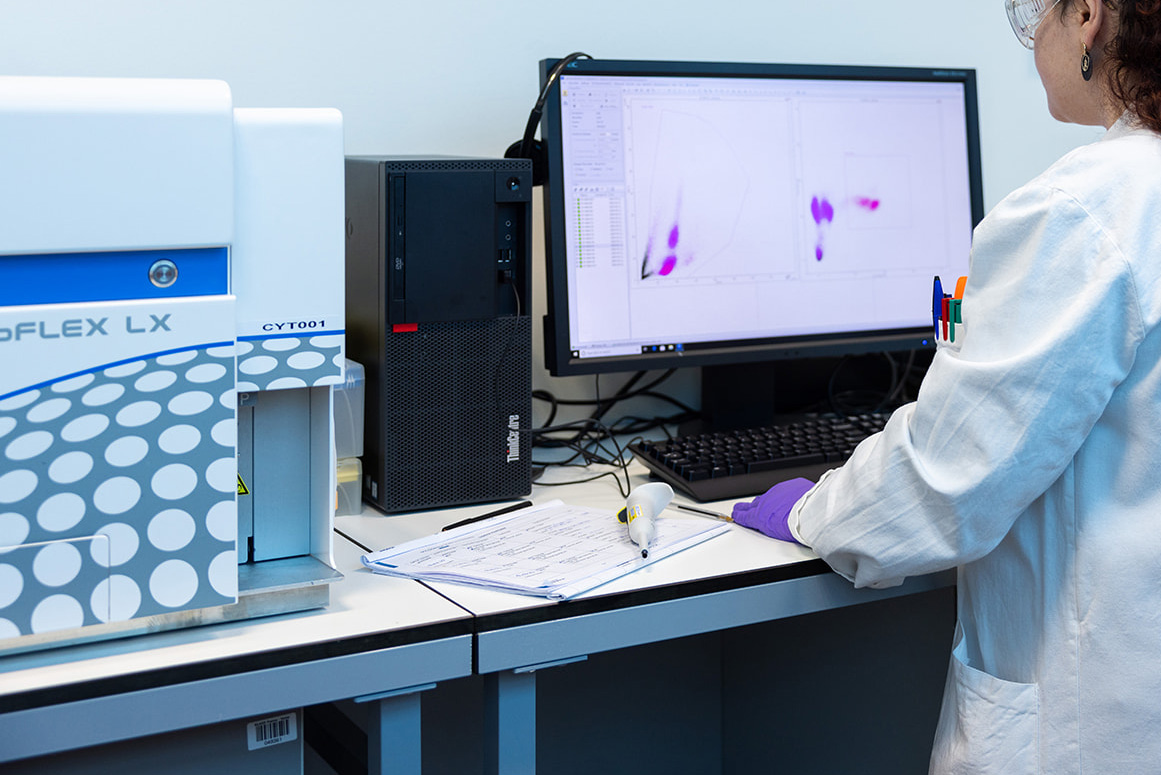

In this service sheet, we introduce the spectrum of colitis models available at Oncodesign Services and explain how we support your project from model selection to data interpretation. By combining established protocols, reproducible endpoints, and translational expertise, we help researchers build solid, clinically relevant foundations for their gastrointestinal inflammation programs.